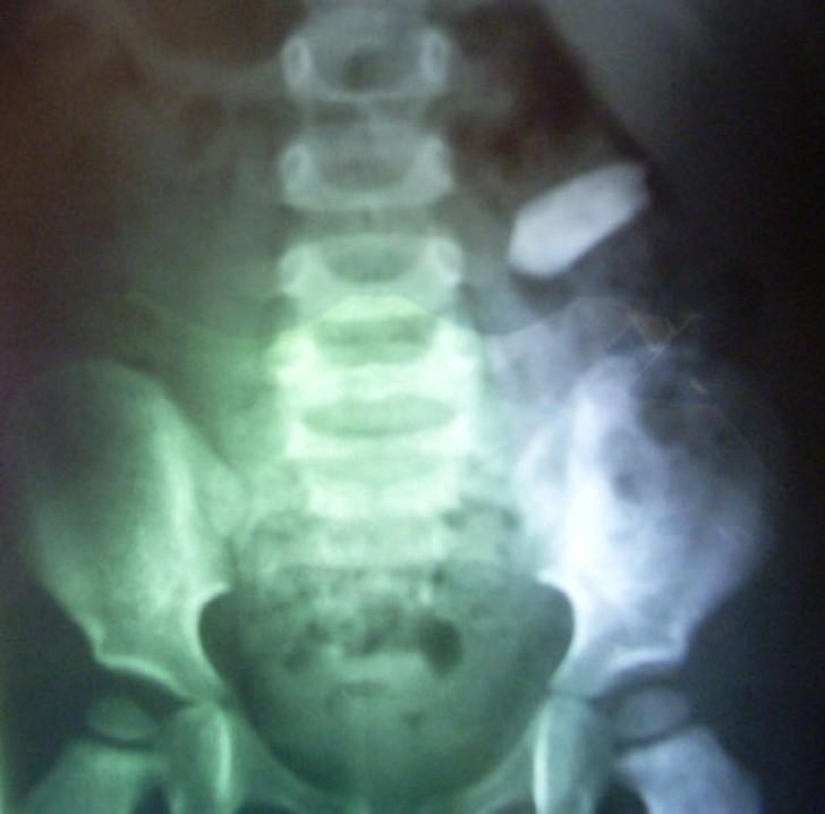

monedas

Imanes.